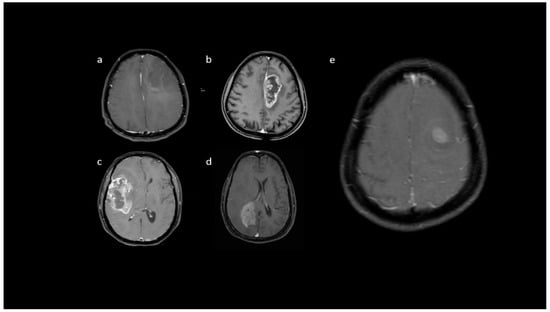

3.2. MRI Parameters of IDH-Wildtype vs. Mutant Phenotype Tumors